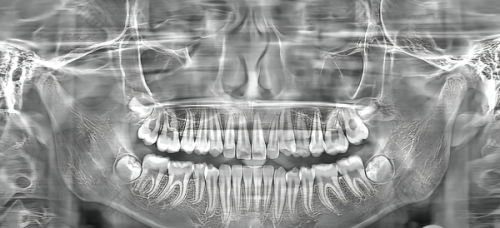

在临沂,要是您正为缺牙问题发愁,那可得好好了解一下临沂柏瑞口腔。这里张龙医生做的韩国仕诺康种植牙,只需1580元起,而且种植体和周围骨组织结合紧密,能大大降低种植后并发症的发生几率,性价比极高!接下来,咱们就详细了解了解。

首先,从种植体本身来说,韩国仕诺康植体采用精良的四级纯钛材质,表面经过SLA大颗粒喷砂处理,这可不得了,能让骨结合速度提升40%。啥意思呢?就是种上牙之后,种植体和咱们的牙槽骨能更快地长在一起,牙齿更稳固。

而且,它和周围骨组织的结合更加紧密。这就好比盖房子,地基打得牢,房子才能更结实。种植体和骨组织结合紧密,牙齿使用起来就更稳定,也降低了种植后并发症的发生几率,让咱们少遭不少罪。

在手术技术方面,临沂柏瑞口腔采用数字化导板种植技术。通过CBCT扫描前期数据收集,医生能在手术中精细把握种植体的角度与深度,误差小于0.1mm。这就像有了导航,种牙更精细,还能减少创伤,手术时间也能缩短至15分钟/颗,术后修复也更快。